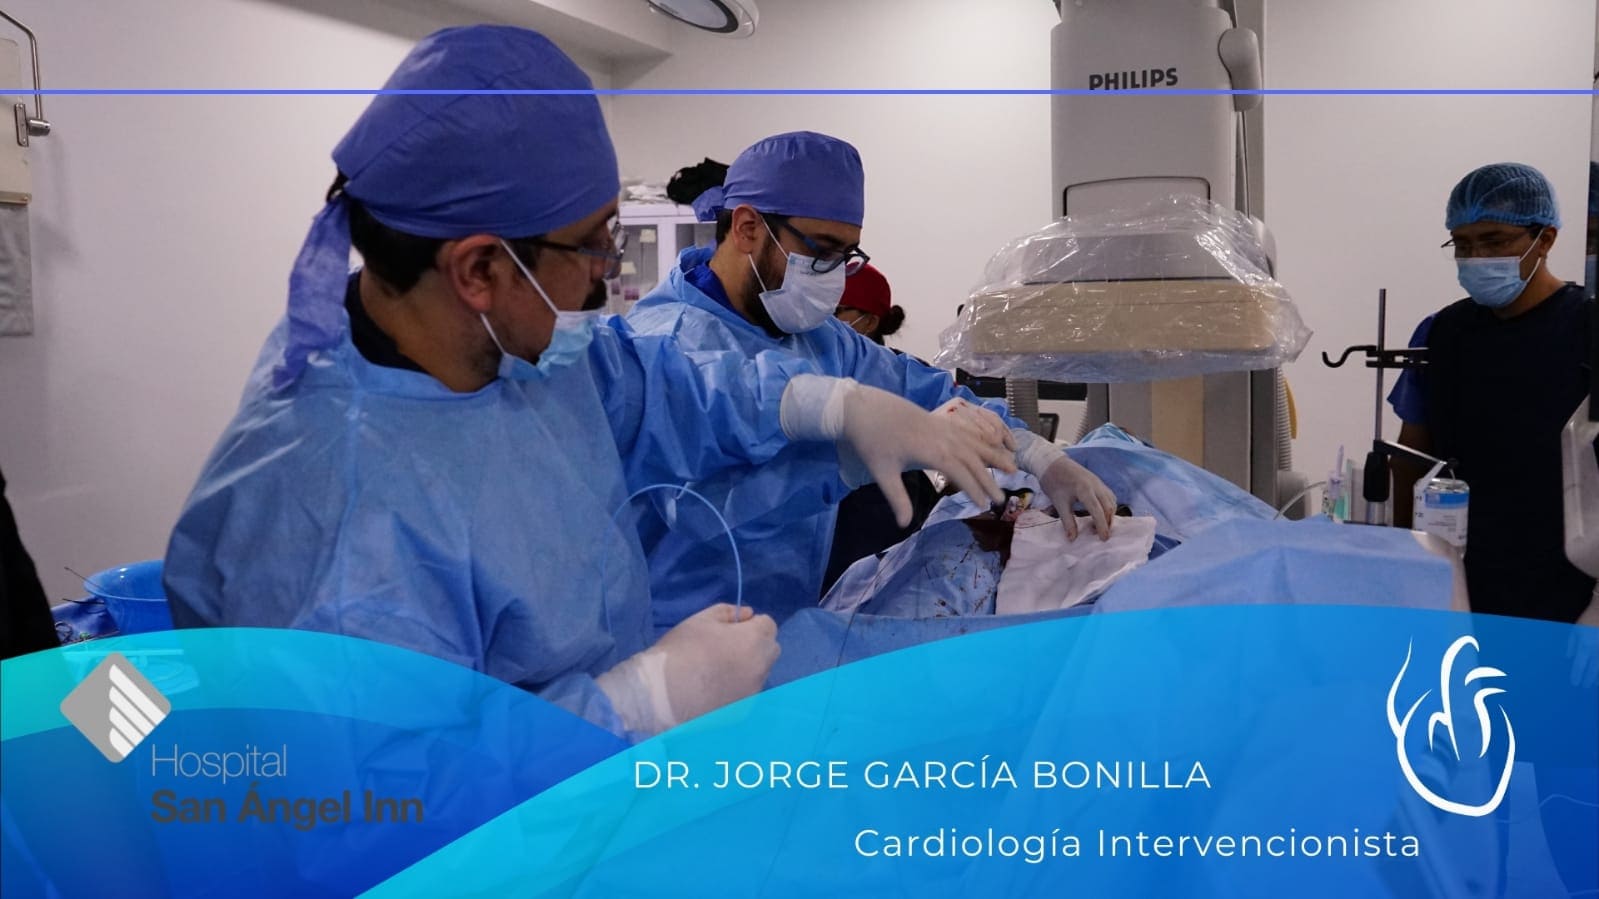

Cardiología intervencionista

Dr. Jorge García Bonilla

Cardiología intervencionista en CDMX

El Dr. García Bonilla es un prestigioso cardiólogo intervencionista con amplios años de experiencia. Se especializa en enfermedades cardiovasculares, trastornos del ritmo cardíaco, enfermedades de la válvula cardíaca, e insuficiencia cardíaca.

Conoce mis instalaciones y algunos casos de pacientes en mi